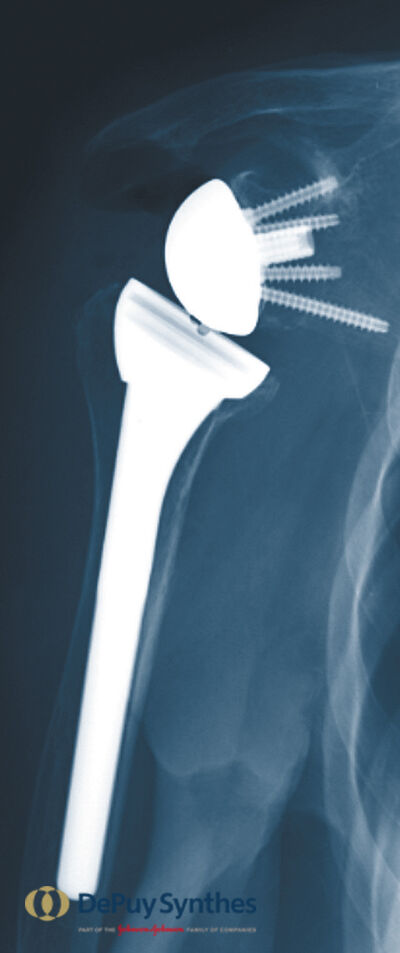

Ist eine gelenkerhaltende Therapie nicht mehr möglich, besteht bei entsprechendem Leidensdruck und Minderung der Lebensqualität die Möglichkeit der endoprothetischen Versorgung

Abhängig von der Ursache der Arthrose und des Lebensalters des Patienten kommen hier verschiedene Prothesenmodelle zum Einsatz.

Verschiedene Varianten stehen zur Verfügung:

- Die Schulterkappenprothese:

- Die anatomische Schultergelenksendoprothese mit Schaft und Ersatz der Gelenkpfanne

- Die inverse Schultergelenksendoprothese: